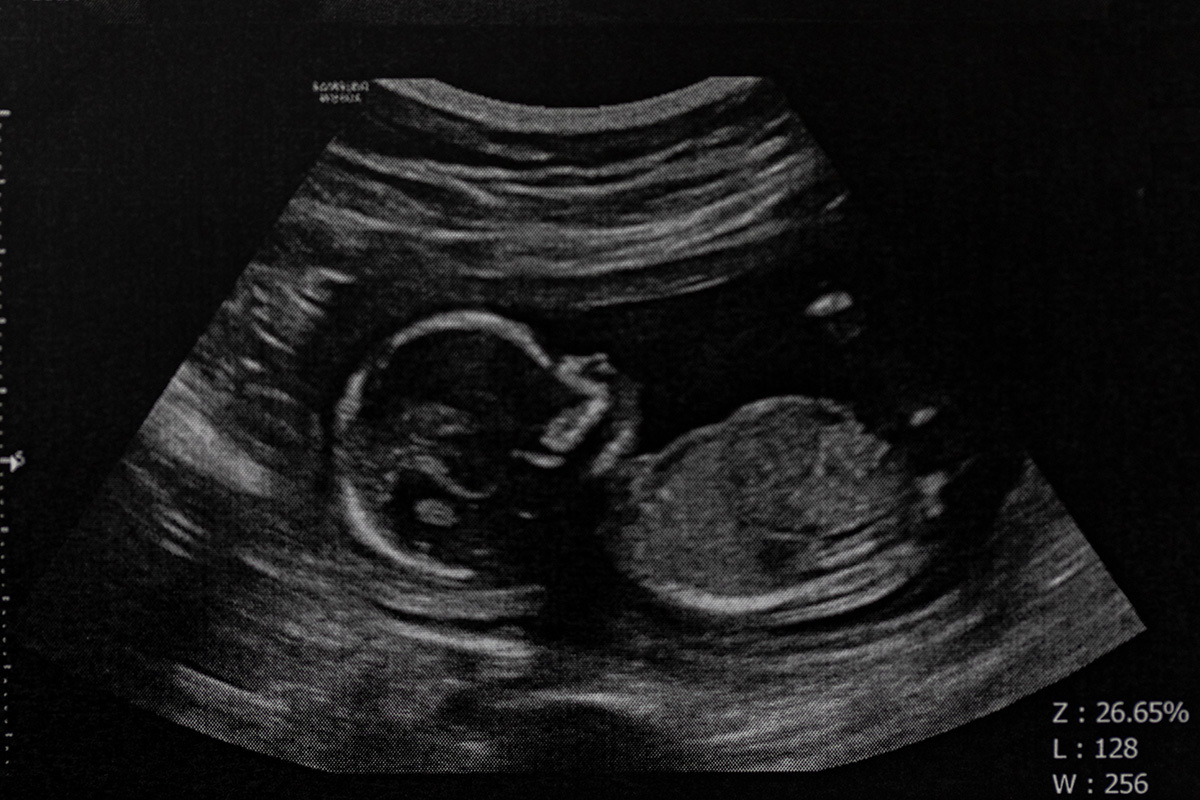

Woman sues abortionist for $250K over perforated uterus, dead baby’s skull fragments in intestine